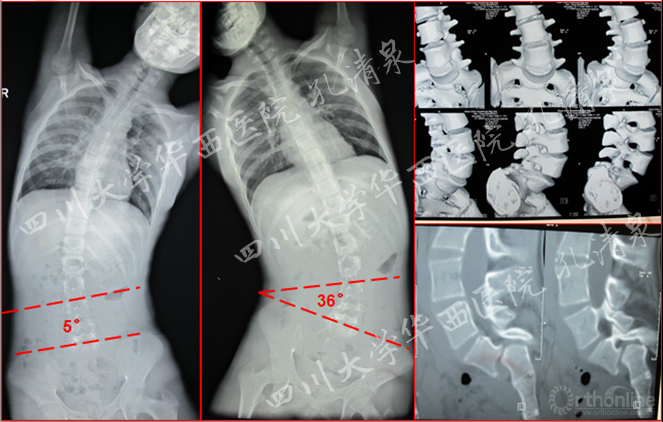

图1 术前X线示:腰5椎IV度滑脱并脊柱侧凸,颈胸弯中立位16°,减轻位0°,胸弯中立位50°,减轻位12°,腰弯33°,减轻位5°,均为非结构性弯。

图2 侧弯的左右bending位摄片及腰骶部CT的矢状面重建及表面重建